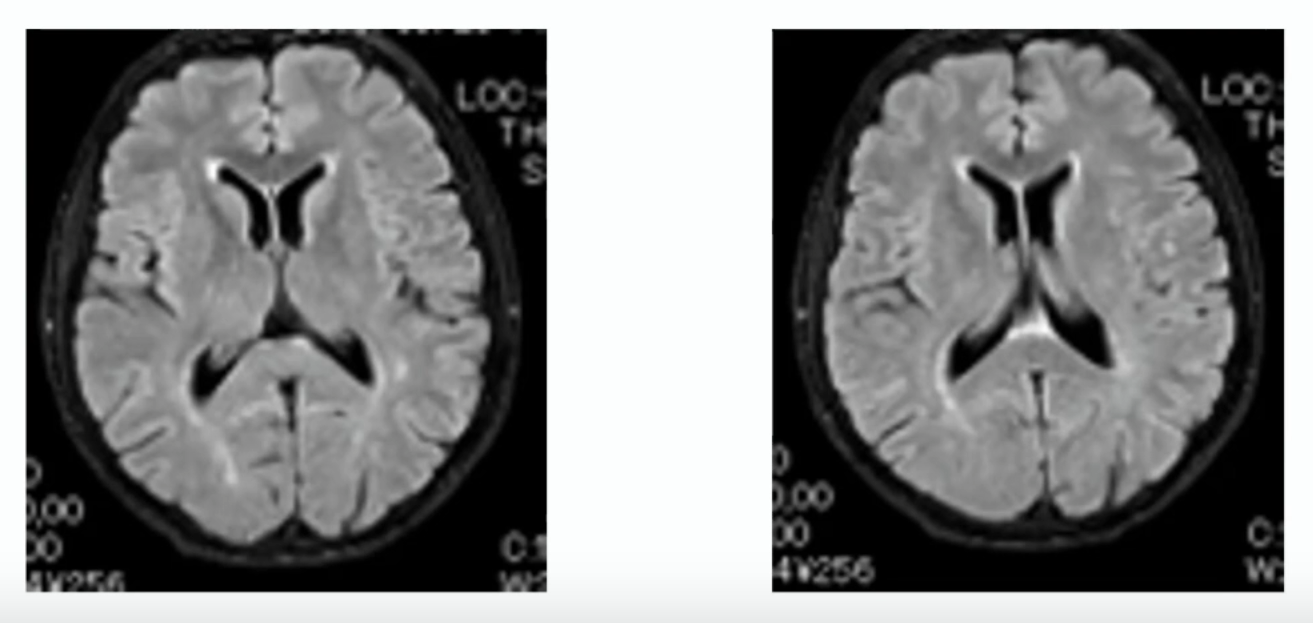

МРТ головного мозга:

диффузные изменения белого вещества (лейкоареоз) – «перивентрикулярное свечение» вокруг передних и задних рогов боковых желудочков

Учитывая данные нейровизуализации и результаты нейропсихологического тестирования, больному поставлен диагноз: хроническая ишемия головного мозга.